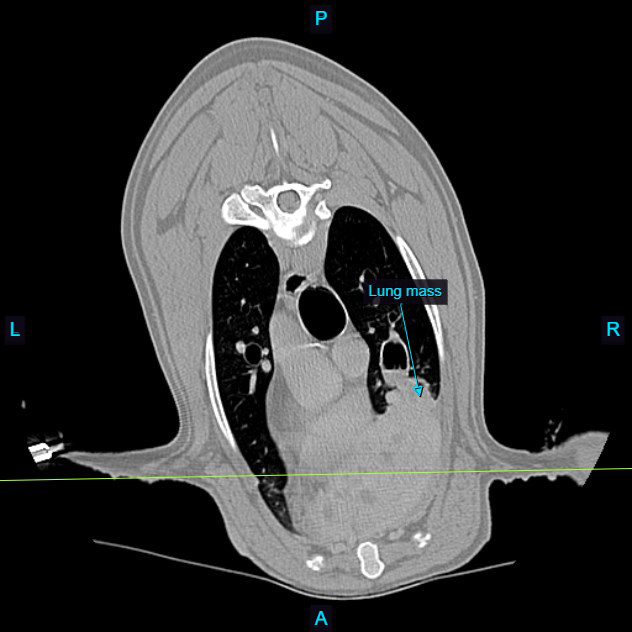

She was seen by Dr. Cletzer on 1-15 for a CT scan and aspirates of the mass. The CT revealed that the mass involved the ventral aspect of her right cranial lung lobe, with local extension into her mediastinum (the tissues in front of the heart and below the lung lobes). Initial cytology raised concern for carcinoma.